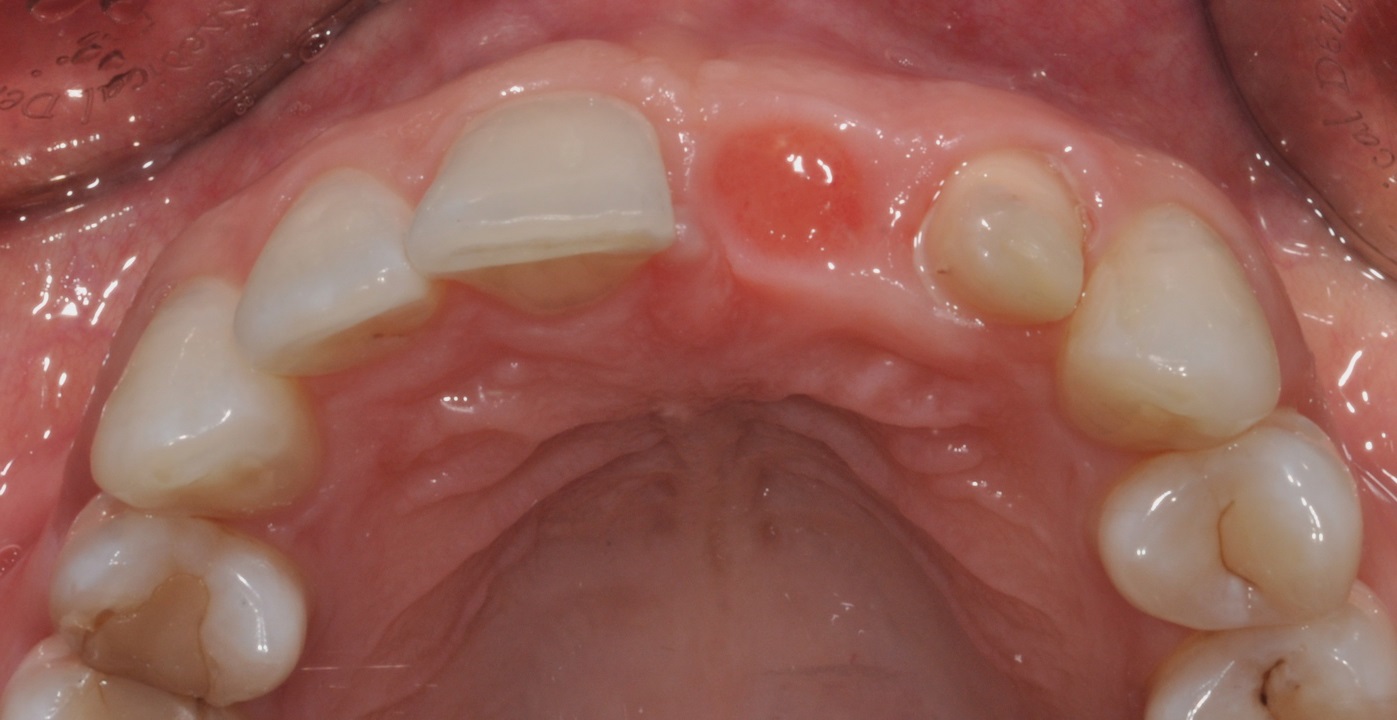

02/16 - Situation before extraction, occlusal view